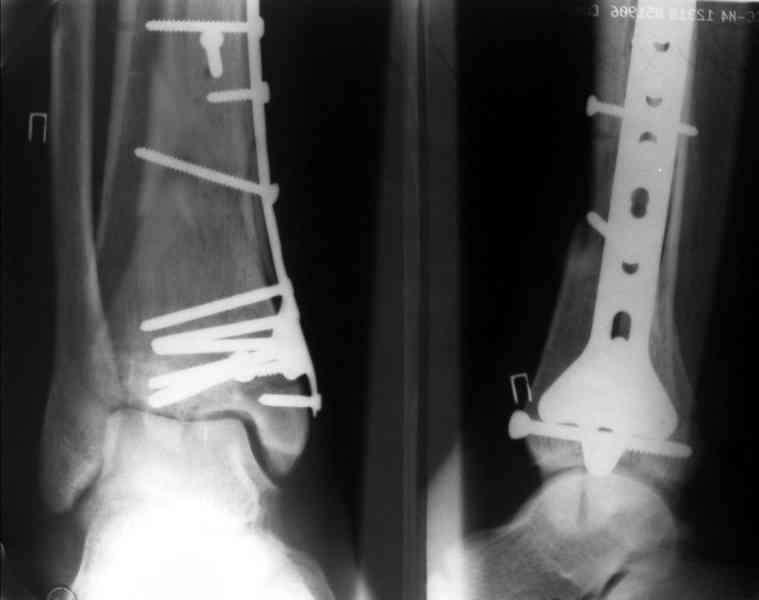

Re: Perelom N/3 kostei goleny

Дрягин В. 04 Январь 2007, 13:28

Кстати, при переломах переднего края по классификации АО В-3 при переломах пилона пластина укладывается по передней поверхности. Она достаточно тонкая и эластичная, не надо этого бояться. Посылаю три снимка.